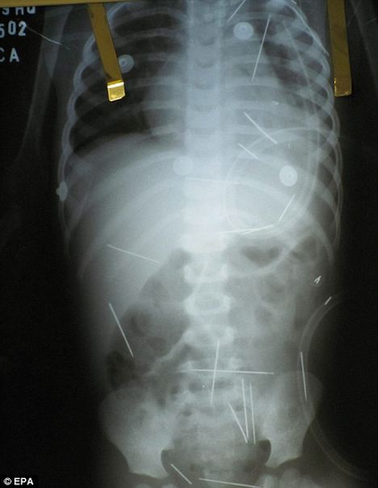

孩子體內的一根根縫衣針令人觸目驚心

中國日報網消息:綜合英美媒體12月16日報道,日前,巴西東北部巴伊亞州的巴雷拉斯醫院接診了一名年僅2歲的小男孩,他自稱渾身不適。經X光片檢查,醫生驚異地發現男童體內竟有50根縫衣針。醫生懷疑,這些針可能是有人惡意扎進男孩體內。目前警方經過初步調查,已經確定男孩的前繼父和另外兩名婦女是本案首要嫌疑人。

主治醫生路易斯表示,通過X光片看到孩子體內竟然有50根縫衣針,他們真是大吃一驚,有好幾根針甚至長達5厘米,但是孩子身體表面卻看不出任何傷口。路易斯說:“這些針肯定是被人一根一根扎進體內的。我們在孩子的肺、左腿和胸腔都發現很多針,根本就不可能是孩子自己吃下去的?!?/p>

據醫生介紹,借助手術他們可以取出一些針,但是有幾根恐怕只能一直呆在男孩體內了,因為它們離孩子的重要器官太近,取針反而十分危險;而扎在孩子肺部的那幾根針,也得等到孩子的呼吸穩定了之后才能動手術取出。